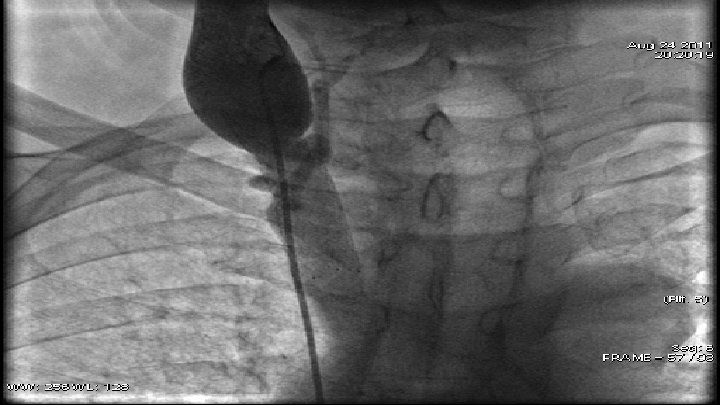

Case 2 q 59 y. o. patient q June 2011 - diagnosed with small-cell lung cancer q August 2011 - angiographic data of subtotal occlusion of VCS. q. PTA – baloon dilatation and stent implantation